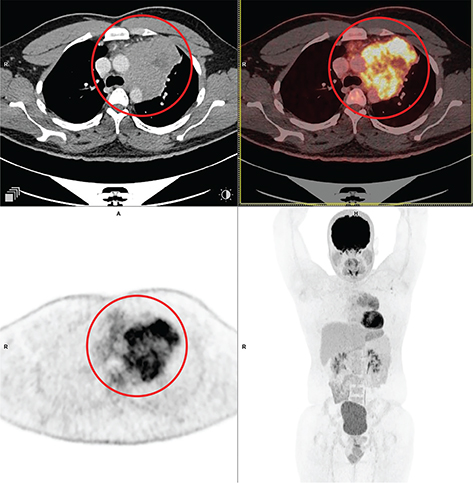

Fig 2

Figure 2. Thymic carcinoma. Anterior mediastinal mass that was pathologically confirmed as thymic carcinoma. FDG PET/CT images include axial CT (top left panel), fused axial PET/CT (top right panel), axial PET (bottom left panel), and maximum intensity projection (MIP) PET image (bottom right panel). In the red circle, there is a soft tissue density mass with irregular nodular contour showing heterogenous enhancement in CT with heterogenous FDG uptake on PET. There is loss of intervening fat plane with the body of sternum anteriorly and the pulmonary trunk posteriorly concerning for infiltration. There was additional mild to moderately FDG-avid regional lymph nodes and pleural deposits (not on the included PET/CT images and could be appreciated on the MIP image) that were suggestive of metastatic disease.